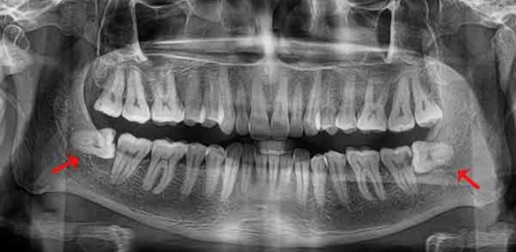

Les troisièmes molaires, aussi appelées dents de sagesses, sont les dernières dents à faire leur éruption dans la bouche, habituellement entre 18 et 24 ans.

Elles sont souvent confrontées à un manque d’espace qui les empêche de prendre leur place convenablement sur l’arcade dentaire.

Il est recommandé de faire un suivi de l’évolution des dents de sagesses à l’aide d’une radiographie panoramique tous les 5 ans. Si un problème est détecté, l’extraction des dents de sagesses concernées vous sera suggérée.